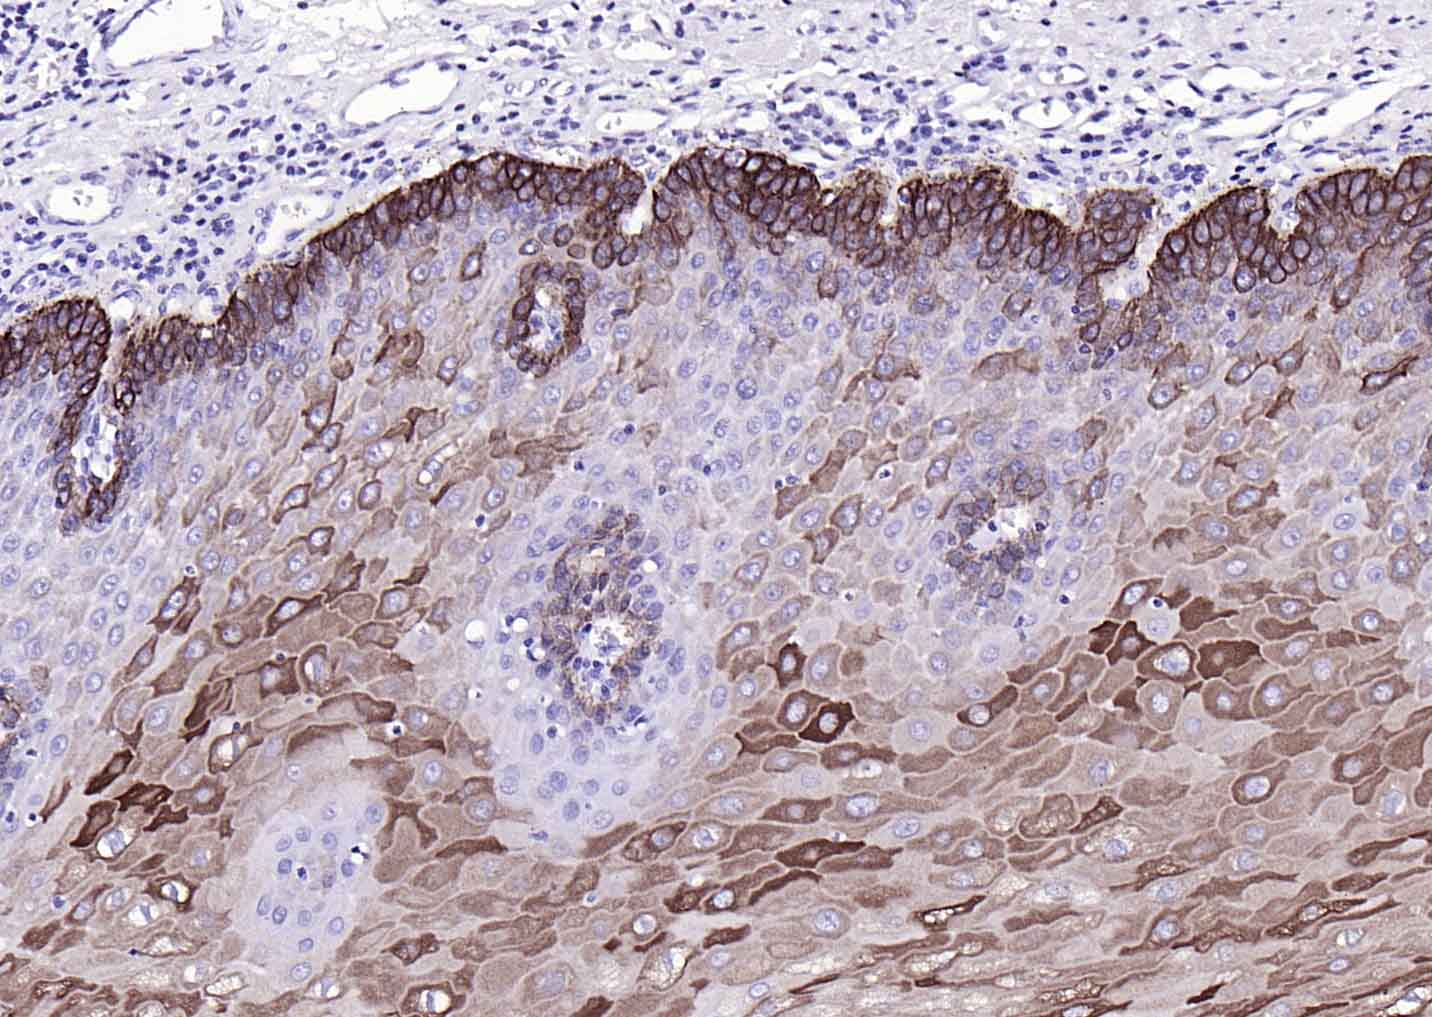

CK17 Mouse mAb

IHC-PHuman1:100-500

组织特异性

Expressed in the outer root sheath and medulla region of hair follicle specifically from eyebrow and beard, digital pulp, nail matrix and nail bed epithelium, mucosal stratified squamous epithelia and in basal cells of oral epithelium, palmoplantar epidermis and sweat and mammary glands. Also expressed in myoepithelium of prostate, basal layer of urinary bladder, cambial cells of sebaceous gland and in exocervix (at protein level).

May play a role in the formation and maintenance of various skin appendages, specifically in determining shape and orientation of hair. May be a marker of basal cell differentiation in complex epithelia and therefore indicative of a certain type of epithelial 'stem cells'. May act as an autoantigen in the immunopathogenesis of psoriasis, with certain peptide regions being a major target for autoreactive T-cells and hence causing their proliferation. Required for the correct growth of hair follicles, in particular for the persistence of the anagen (growth) state. Modulates the function of TNF-alpha in the specific context of hair cycling. Regulates protein synthesis and epithelial cell growth through binding to the adapter protein SFN and by stimulating Akt/mTOR pathway. Involved in tissue repai.